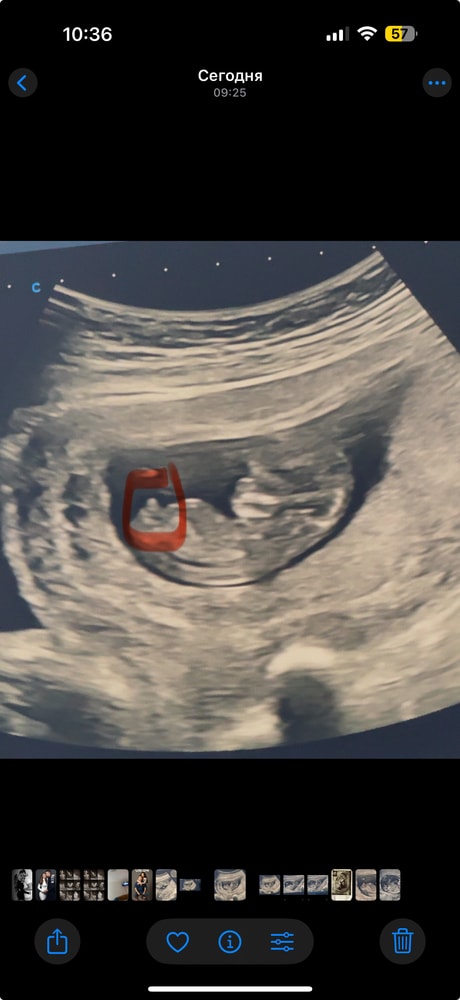

1 скрининг ,Мальчик наш🥹❤️

СкринингПервый скрининг пройден на отлично 🥹😍Моя 4 Ая беременность 😍🥹🥹🥹

сказали со здоровьем все хорошо,и Мальчик 80-90% 😍😍😍🥹🥹🥹🥹

После 3 девочек наш Принц идет 😭

вы тоже видите что Мальчуган?))

срок тут по узи 11,5 дней